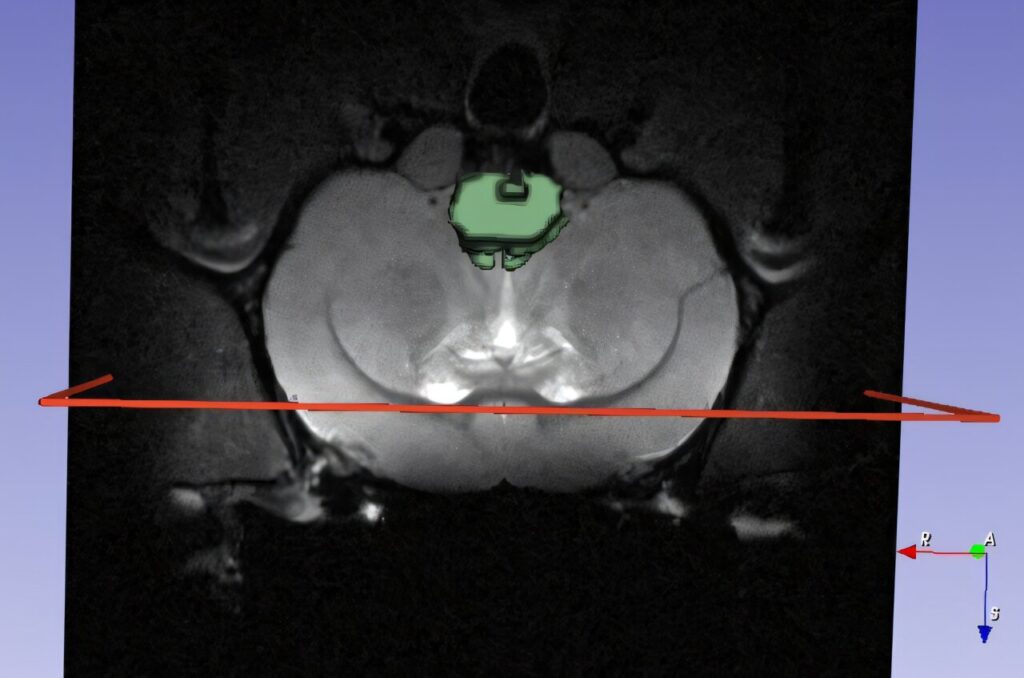

That’s where molecular imaging (MRI, PET, and contrast agents) meets a machine learning approach. We can monitor “where nanomedicines go, how much reaches the target tissue, and what biological effect it has,” by incorporating imaging data and training AI/ML models.

In our review, we have provided detailed information on how imaging-based biomarkers and ML algorithms can substantially help in optimization of nanomedicine frameworks, such as selecting particle size, coating, targeting moieties and release kinetics.

Later, we analyzed patterns of nanoparticle uptake across regions with AI and adjusted the particle architecture accordingly. It’s this cycle, design → image → AI-driven feedback → redesign, that defines the successful interdisciplinary approach for the patient-centric treatment of neurodegenerative diseases.

If you’re in the field of nanomedicine, it is time to partner with imaging experts and AI specialists. In our lab, we are currently synthesizing novel nanoparticles and developing AI models capable of predicting optimal nanomedicine dosages from MRI images of mouse brains.